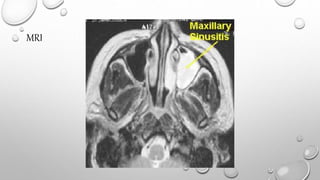

COMPUTERIZEDTOMOGRAPHY (CT) & MAGNETIC

RESONANCE IMAGING (MRI)

• THESE MODALITIES PROVIDE MULTIPLE SECTIONS THROUGH THE

SINUSES AT DIFFERENT PLANES AND THEREFORE CONTRIBUTE TO

THE FINAL DIAGNOSIS AND THE DETERMINATION OF EXTENT OF

THE DISEASE.

CT SCAN

MRI